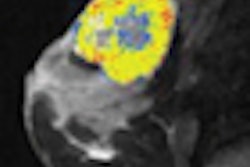

We examine how to spot signs of crack abuse on chest images in an article this week by staff editor Heather Hokenson. The story reviews the clinical research on "crack lung," describing the condition's distinct presentation on chest radiography and CT images.

Crack lung can mimic other lung pathologies, such as pulmonary embolism and sarcoidosis, and diagnosis can also be complicated by the fact that addicts may not disclose their drug use when giving their patient histories. Find out how you can spot the condition by clicking here, or visit the Digital X-Ray Community.